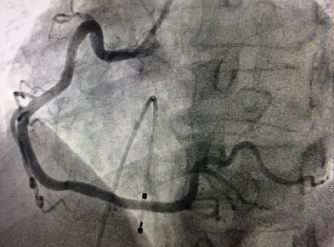

术后右冠动脉近端完全开通

手术台上,老人心率进行性下降到40次/分左右,病情极其危重。心内科介入手术团队迅速为患者植入心脏临时起搏器,在临时起搏器的保护下,医生从血管穿刺开始仅耗时15分钟就完成了冠脉造影术,但检查结果十分不乐观:右冠状动脉自近端完全闭塞,可见血栓影,袁小蓉立即采用特殊的药物替罗非班注射液10ml在冠脉内推注。在数分钟内,医生迅速、准确的为将导丝通过闭塞段,采用血栓抽吸导管进行血栓抽吸,植入支架,打通右冠状动脉血管,手术成功了!

支架植入成功后,老人的胸痛病状立即缓解,术后意识清醒,经过药物调养后,心率逐渐恢复正常,6天后下床活动。4天后,张大爷的身体得到了一定的恢复,又进行了另外一支重度狭窄血管(回旋支)的球囊扩张加支架植入术,手术过程很顺利,仅用时不到一小时。术后4天,老人康复出院。